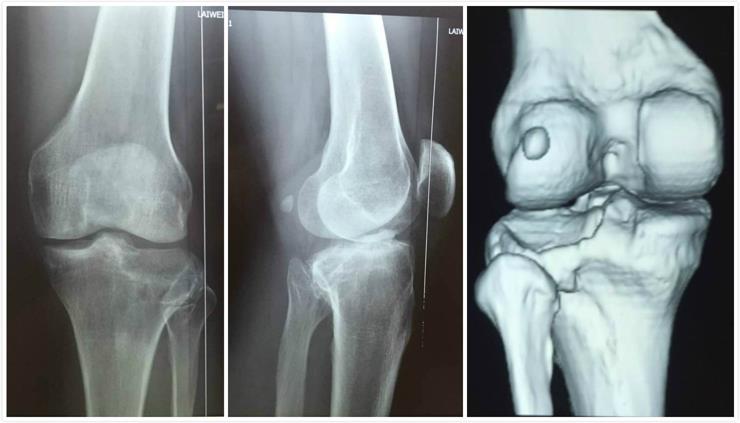

男性病人,43歲,左脛骨平臺后外側(cè)塌陷骨折。

術(shù)前影像學(xué)資料:

- 模擬病人骨折,讓醫(yī)生更直觀的了解骨折情況